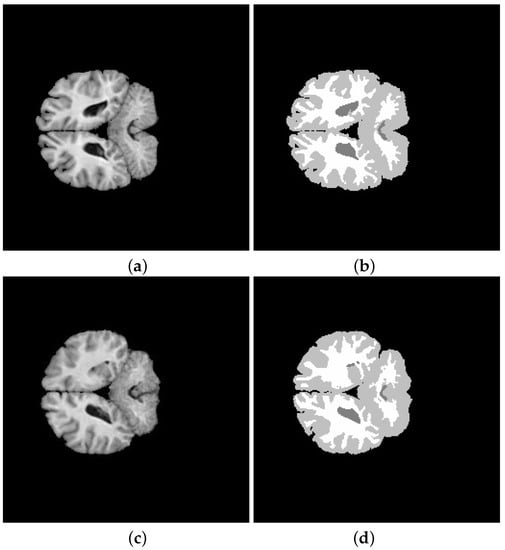

5. Application and Results